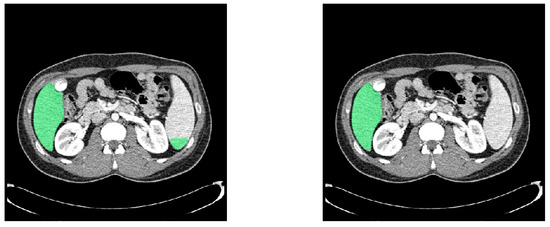

4.3. Post-Processing